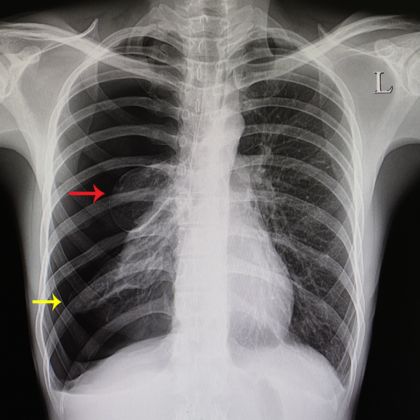

• Zdjęcie rentgenowskie klatki piersiowej: Jednym z podstawowych badań obrazowych stosowanych w diagnostyce odmy opłucnowej jest wykonanie zdjęcia rentgenowskiego klatki piersiowej. Na zdjęciu można zaobserwować obecność powietrza w przestrzeni opłucnowej oraz ewentualne zmiany w strukturze płuc i opłucnej.

• Tomografia komputerowa: W przypadku wątpliwości co do diagnozy lub konieczności dokładniejszego zobrazowania zmian w klatce piersiowej, może być zalecane wykonanie tomografii komputerowej. Ta bardziej zaawansowana technika obrazowania pozwala na dokładniejszą ocenę stanu klatki piersiowej i struktur anatomicznych.

• Ultrasonografia (USG) klatki piersiowej: Badanie ultrasonograficzne klatki piersiowej może być przydatne do oceny obecności płynu lub powietrza w przestrzeni opłucnowej. USG pozwala na dynamiczną ocenę stanu pacjenta i może być przydatne zwłaszcza w warunkach pilnych.